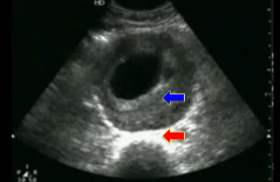

Disregarding the arrows, what pathology is seen here?

Aneurysm (thrombus)